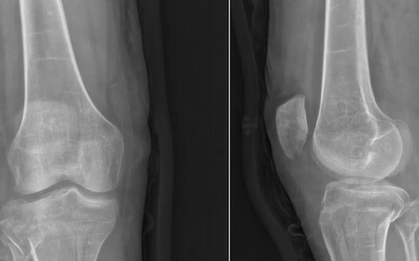

Xem x-quang xương của "bà cụ 80 tuổi" bị gãy đốt sống, bác sĩ ngớ người khi biết bệnh nhân mới ngoài đôi mươi

Sức khỏe

-

Nếu cho rằng loãng xương là bệnh của người già thì bạn đã lầm. Đôi khi, tuổi thật của bạn là ngoài đôi mươi nhưng tuổi xương tương đương bà lão.